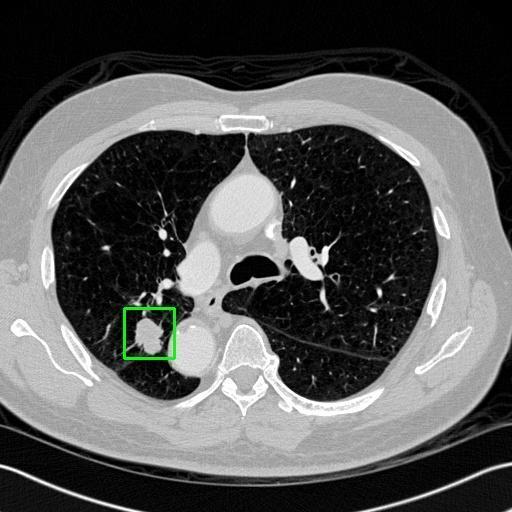

We developed an AI-based system using deep learning models for analyzing lung CT scans to detect and classify pulmonary nodules. We chose the YOLOv11 architecture for its enhanced object detection capability and adapted it specifically for medical imaging, incorporating pixel-level precision and severity classification.

Classification into three severity levels with colored bounding boxes.

Designed a severity classification system that categorizes nodules into null, moderate, and severe using colored bounding boxes, assisting in rapid clinical decision-making.